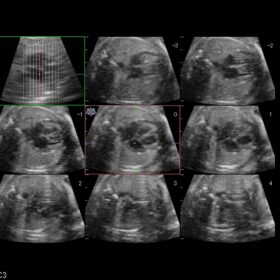

Ultrasound ARIETTA V60 – Image Gallery and Videos

Obstetrics 2D, Color and 4D mode

- In obstetrics, the 4D display is a communication tool which can encourage the bond between mother and fetus, and strengthen family ties.